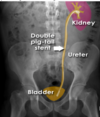

**What is the artifact shown in this image?** Naso-jejunal tube Colonic stent Pig-tail (JJ) stent Percutaneous nephrostomy tube Inferior vena cava (IVC) filter

**Pig-tail (JJ) stent** A ureteric stent has been placed to relieve ureteric obstruction The catheter has loops (pig-tails) at both ends which hold it in place